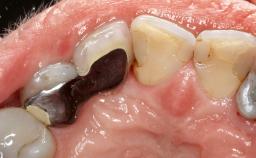

Peri-Implant Mucositis Treatment Outcomes on an Implant with a Submucosal Restoration Margin

Mauricio Araujo and Flauvia Matarazzo present this straightforward clinical case, demonstrating the potential effect of implant placement depth on the resolution of peri-implant treatment. A 42-year-old systemically healthy female patient, a non-smoker with no history of periodontitis, was treated at the Dental Clinic at the State University of Maringá, Brazil between 2008 and 2009, when she received five implants restored with single crowns at sites 14, 26, 27, 36, and 46. After delivery of the implant-supported prosthetic restorations, the patient was enrolled in the supportive peri-implant therapy (SPiT) maintenance program at the same university.